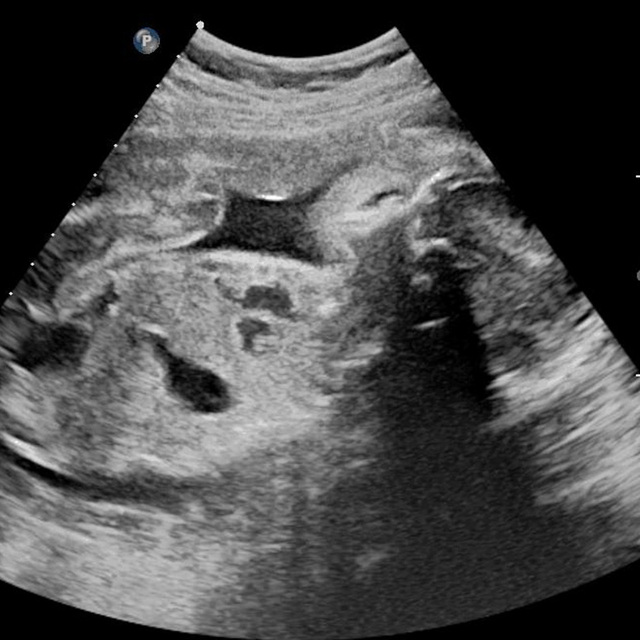

终于轮到我了。我绷紧神经,先到床头拿了一张纸放在床中央,坐上去准备脱右腿裤子时,突然发现自己穿了靴子,两只都脱,会耗时过长,大脑飞速转过医生等得不耐烦的样子,顿时慌乱了。“两只鞋子都要脱吗?”我问医生,问完我就后悔了。等待她的回答很漫长,长到我有足够时间把它们都脱下来。医生最终也没理我,撕开一个好像安全套似的袋子,取出套子,套在一根长长的检查器上,然后板着脸把它插进阴部。

我的心情非常复杂,不敢喊疼又有些恐惧。“多大了?”医生面无表情问我。“我吗?”我不清楚她问的是我,还是腹中的胎儿。

“几个月了?”她补充了一句。

“我不知道,医生没说,我自己查是5周。”

“还看不到。”她拔出检查器,打出检查单,“下一个。”

我的心凉了半截,慌乱穿好裤子,接过检查单,再次上楼进了医生办公室,里面已经有七八个人,我学着其他孕妇的样子,把B超单放在白口罩医生桌上,她扫了一眼,小声含糊说:“孕期太小了还看不到,下周再过来复查一次。”然后在打印机上又刷出了四五张单子,递给我:“验血,下周拿报告”。